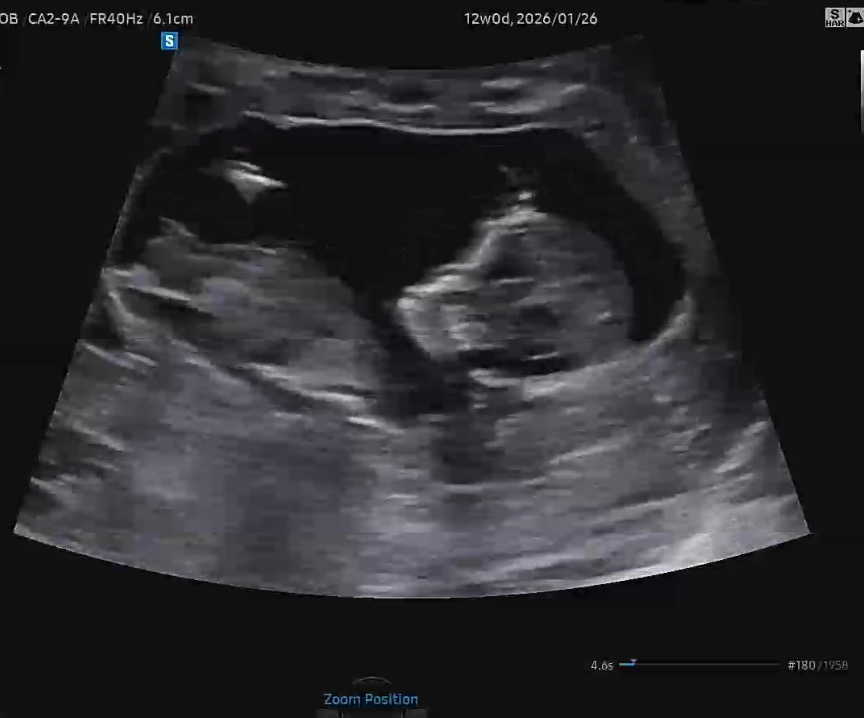

셋째 성별 같이 봐주세용💜

끝이 갈라져서 딸이려나요 각도는 아들같긴한데 어때보이세용?